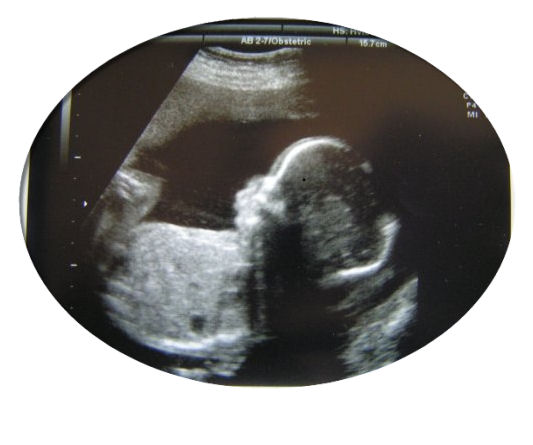

Reconnaissance de l’enfant mort-né : décret en préparation

En février dernier, la cour de cassation avait jugé dans trois arrêts qu’un fœtus né sans vie pouvait être déclaré à l’état civil quel que soit son poids et la durée de la grossesse.

Depuis 1993, l’enfant mort-né ne peut avoir de déclaration « d’enfant sans vie » que si il pèse plus de 500g ou que la grossesse a duré plus de 22 semaines. L’enfant né sans vie est malheureusement considéré comme un déchet organique et est incinéré à l’hôpital.

enfant grossesse

Actuellement, le ministère de la santé prépare un décret pouvant permettre l’inscription d’un enfant mort-né sur le registre de l’état civil sur la base d’un certificat d’accouchement.

Après avoir entendu le cœur de son bébé battre, après l’avoir vu bouger, il n’y a rien de plus normal pour des parents que de voir le nom de leur enfant malgré qu’il soit mort-né, inscrit sur son livret de famille !

Après le témoignage de Eve-Marie et les commentaires suscités, ce décret va peut être apporter un plus dans le processus de deuil des parents.